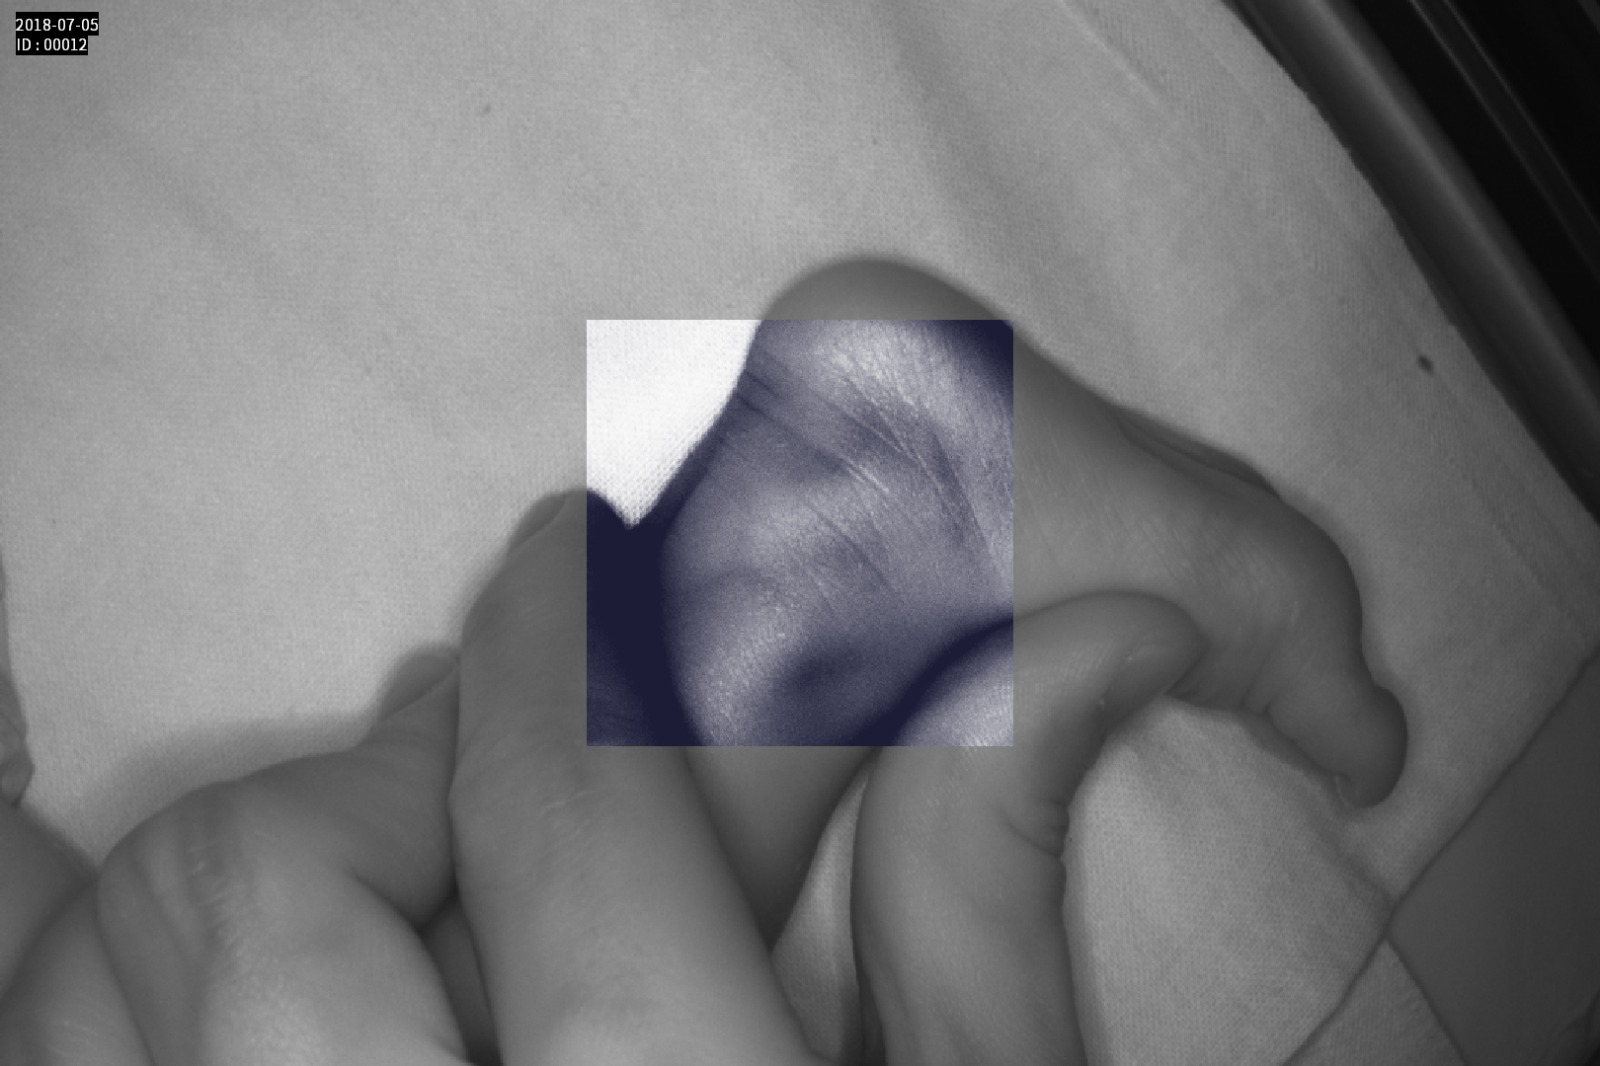

Dispozitiv medical portabil, non-contact, ce ajută la vizualizarea venelor pentru efectuarea puncției venoase, intervențiilor chirurgicale plastice, diagnosticul venelor varicoase.

Grad mare de detecție a venelor greu vizibile până la 10 mm adâncime (inclusiv vene faciale)

Imaginea venelor este proiectată pe monitorul propriu în timp real si ajută la identificarea corectă și precisă

Multiple aplicații de vizualizare vene atât la sugari cât și la pacienții obezi sau în urgențe indiferent de tonul de culoare a pielii